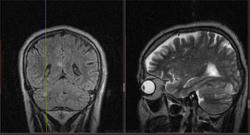

Мужчина 1964 г.р. Жалобы на нарушение памяти, снижение зрения и кратковременную потерю сознания, температура нормальная.

Я думаю что это может быть какой нибудь васкулит, либо Posterior Reversible Encephalopathy Syndrome, о чем можно думать в данном случае?

Контраста нет. Дайком тут!

eto pres

Я представлял синдром с более выраженным изменением сигнала от белого вещества и меньшим - коры.